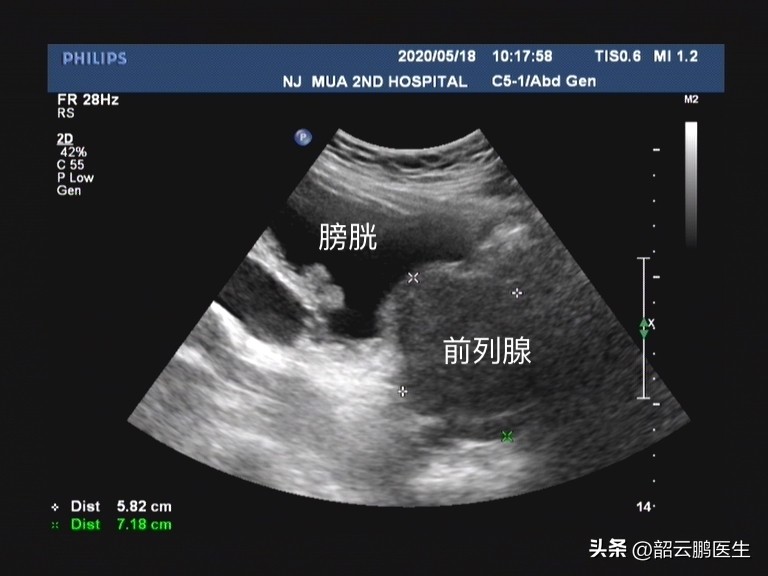

水蒸气消融仍然是存在 很多限制条件的 , 比如对于中叶突出明显或者前列腺向膀胱内凸出的患者 ,单纯的水蒸气消融是没有办法处理的,仍然需要依靠电切或者激光等手术方式将这部分组织切除。